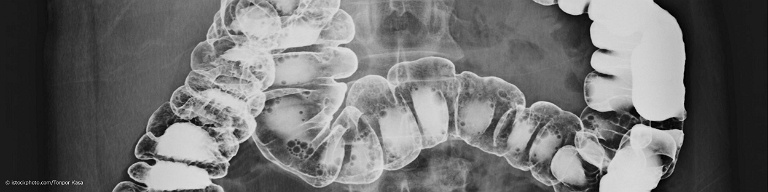

Kontrastmitteldarstellung des gesunden Dickdarms (Kolon) eines männlichen Patienten.

Kontrasteinlauf

Die Darstellung deines Dickdarms (Kolon) mit Hilfe eines rektal verabreichten Kontrastmittels und Röntgen wird angewandt, wenn mit einem Endoskop bei einer Darmspiegelung aufgrund von Entzündungen oder Verengungen bestimmte Darmabschnitte nicht eingesehen werden können. Der Kontrasteinlauf ist in der Regel schmerzfrei und braucht eine gewisse Vorbereitung.